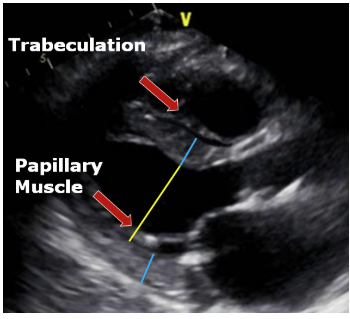

LV biplane measurement

Straight line at MV level-height from midpoint Do NOT include papillary muscles or trabelculations No forshortening LV length perpendicular to base